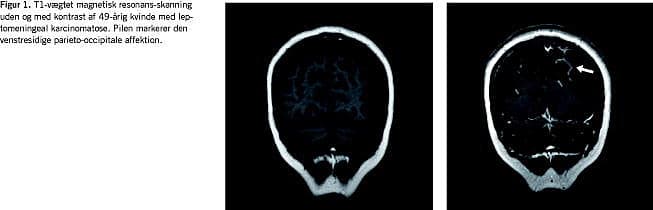

Ved indlæggelsen var patienten i god almentilstand, og de eneste objektive fund var bilateral hørenedsættelse. Samtlige rutineblodprøver var upåfaldende. En computertomografi (CT) af cerebrum med kontrast blev initialt tolket som vi-sende normale forhold, men efterfølgende revidering af bil-lederne gav mistanke om LC. Mistanken blev skærpet ved supplerende magnetisk resonans (MR)-skanning af cerebrum med kontrast (Figur 1 ), der viste meningeal opladning parie-to-occipitalt bilateralt, hvilket er foreneligt med LC. Under-søgelse af cerebrospinalvæsken (CSF) gav følgende resultater: 60 × 106 /l leukocytter med 90% af mononukleær type, CSF-protein 0,8 g/l og CSF-glukose 1,7 mmol/l (serumglukose 5,2 mmol/l). Der kunne ikke påvises maligne celler i CSF.

Til yderligere belysning af diagnosen kan billeddiagnostikken anvendes, hvor MR-skanning med kontrast (sensitivitet 70%) har vist sig at være mere sensitiv end CT [1, 4]. Disse billeddiagnostiske undersøgelser er dog ikke i sig selv diagnostiske, da meningeal kontrastopladning kan være udtryk for andre tilstande som f.eks. inflammation/neuroinfektion.